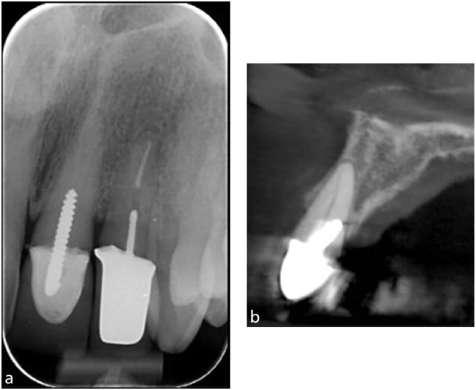

Among the more challenging treatments are those related to bringing impacted teeth into the arch. Often these teeth are engaged with other teeth, so the orthodontist must be aware of the vector of force needed to move the tooth without causing resorption of the roots of adjacent teeth or other problems. The orthodontist must inform the patient and parents about the risks and alternative approaches to recovering impacted teeth before treatment is begun. In addition, the orthodontist should obtain cone-beam computed tomograms of the area to aid diagnosis and treatment planning. In some cases, the teeth don’t move or become ankylosed during movement, with reciprocal movement. In these cases the orthodontist must reevaluate the situation before proceeding further.